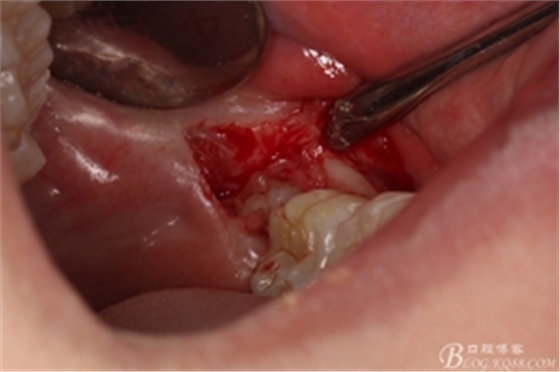

圖10. 翻開瓣。38牙冠還有部分骨質(zhì)覆蓋,遂用高速牙鉆去骨

圖11.去骨---暴露出38的牙冠最大周徑

圖12.高速牙鉆分牙